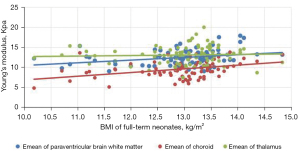

Comparison of Emean of the neonatal brain between premature neonates and full-term neonatesVariables Premature neonates (n=76) Full-term neonates (n=83) Left (kPa) Right (kPa) Mean (kPa) Left (kPa) Right (kPa) Mean (kPa) Lateral paraventricular white matter 10.39±2.10a 10.23±2.08a 10.50±2.04a 12.32±2.14 12.65±2.09 12.49±1.91 Thalamus 11.14±2.33a 11.25±2.07a 11.38±2.16a 13.31±2.49 12.92±2.40 13.11±2.22 Choroid 9.18±2.19a 9.15±2.17a 9.16±2.07a 9.65±2.24 9.62±2.20 9.64±2.08 a, P<0.001 premature neonate group vs. full-term neonate group. Emean, elasticity modulus. - The Pearson’s correlation coefficient analysis showed that the neonatal lateral paraventricular brain white matter, thalamus, and choroid brain tissue stiffness values were significantly and positively correlated with BMI (P<0.05). The correlation coefficients between the lateral paraventricular brain white matter, thalamus, and choroid and BMI were r=0.457, r=0.681, and r=0.462, respectively, for the premature neonate group and r=0.476, r=0.327, and r=368, respectively, for the full-term neonate control group (see Figures 2,3

).

The gray matter of the brain is the dense site of neuronal cell bodies, and the white matter of the brain is the site of nerve fiber aggregation. When the thalamic elastic stiffness values are higher than the white matter stiffness values in the neonatal period, the gray matter structure is denser than the white matter structure of the brain. The development of the central nervous system is an extremely complex and continuous process that involves a dynamic balance between cell proliferation, differentiation, migration, synaptogenesis, myelin formation, and apoptosis of brain neurons and glia. Examinations of correlations between brain tissue stiffness and the degree of cerebral vascular development and cerebral blood perfusion pressure have shown that the denser the neuronal cells, the higher the value of brain tissue stiffness (17). In this study, we analyzed correlations between BMI and brain tissue Emeans in premature and full-term neonates, and found that the higher the BMI, the higher the neonatal thalamus, lateral paraventricular cerebral white matter, and choroid plexus tissue stiffness. Pong et al. (18) used Magnetic resonance elastography (MRE) to examine the cranial brains of rats at 1–6 weeks, and the results suggested that the brain gray matter stiffness of young rats increases with age. Which provides support for the results of the present study.